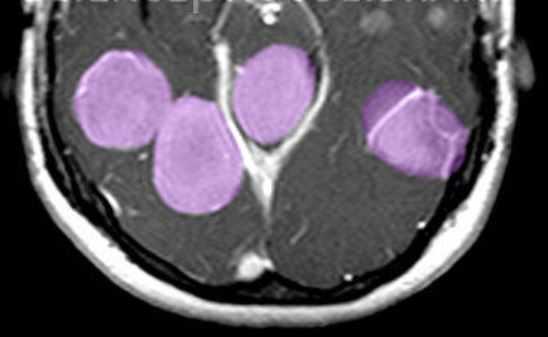

Туберозный склероз. Гамартомы. КТ, Т2-зависимая МРТ и FLAIR

Субэпендимальные, то есть проецирующиеся в желудочек, но растущие со стороны паренхимы мозга, узлы чаще расположены рядом с хвостатым ядром или гипоталамической бороздой сразу за отверстием Монро, реже в области III, IV желудочков и Сильвиева водопровода. На Т2-взвешенных томограммах субэпендимальные узлы умеренно гиперинтенсивны и часто содержат кальцинаты . От астроцитом их отличает не столь яркий сигнал и меньшие размеры. Контрастирование при введении препаратов гадолиния иногда наблюдается и в субэпендимальных узлах , и всегда в астроцитомах.

Туберозный склероз. Субэпендимальные узлы. Аксиальная Т-зависимая МРТ.